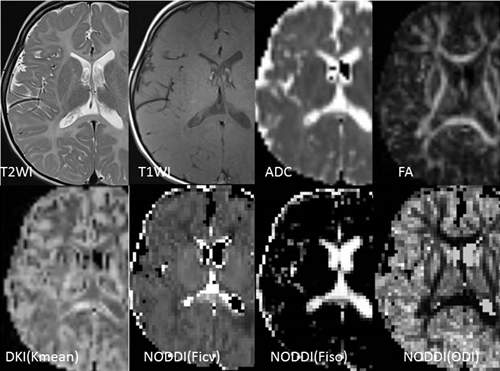

Pelizaeus-Merzbacher病の各種拡散画像。

髄鞘の形成障害を来す疾患である。T2強調像やT1強調像で本来の白質の信号が失われているのがわかる。拡散テンソル法で算出されたADC画像では白質部分の拡散能がやや高くなっている。拡散異方性(FA)画像では白質に沿って高い異方性が認められる。

非正規分布拡散画像の一つである拡散尖度画像(DKI)では、脳梁部分を除き白質の尖度が低くなっているのがわかる。白質内の軸索・樹状突起の密度や方向のばらつきを推定する画像法であるNeurite Orientation Dispersion and Density Imaging (NODDI)では、軸索・樹状突起の密度(Ficv)が全体にきわめて低くなっていることがわかる。一方自由拡散を示す領域(Fiso)や拡散の方向のバラツキ(ODI)に関しては、正常の脳とあまり変わりがない。